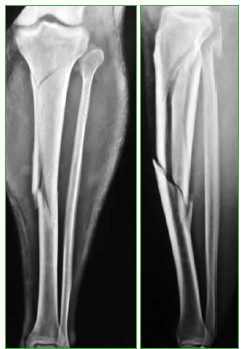

Tratamiento con clavo endomedular de las fracturas metafisarias proximales y distales de tibia. Abordaje pararrotuliano medial en posición de semiextensión